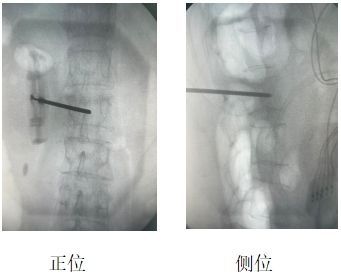

患者辛某(化名),女性,69歲,因“腰部劇烈疼痛伴活動受限2天”入院。既往有骨質疏松癥病史,影像學檢查提示L2椎體新鮮壓縮性骨折,VAS評分8分。

當地醫院建議外科手術治療,患者及家屬拒絕開刀手術,遂來我院疼痛科。結合患者自身情況,劉康主任與科室人員經討論,決定行“經皮椎體成形術(PVP)”聯合“脊神經后內側支射頻調控術”,同時解決椎體穩定性與神經源性疼痛問題。

劉康主任表示,椎體成形術+脊神經射頻調控聯合應用,較傳統單一“骨水泥”植入對緩解疼痛有明顯改善。

兩者微創聯合優勢應用于“椎體壓縮骨折”可單次麻醉、同一體位完成兩項操作,降低手術風險,提升患者耐受性,顯著緩解疼痛,大大減少“骨水泥”植入術后殘余疼痛。 脊神經后內側支射頻是骨質疏松性壓縮骨折(OVCFs)疼痛管理的重要補充。約30%患者“骨水泥”植入術后存在脊神經源性殘留痛,聯合射頻可顯著提升遠期療效。此病例為骨質疏松性骨折的個體化治療提供了新思路。